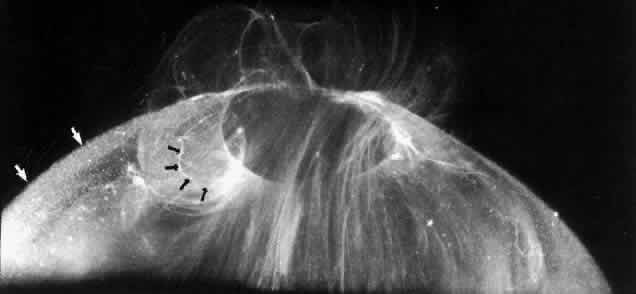

The posterior vitreous cortex is 100-110 μm thick50,60 and, as shown in Figure 12, consists of densely packed collagen fibrils.50,60,152 There is no vitreous cortex over the optic disc (see Figs. 4A AND 13), AND the cortex is thin over the macula due to rarefaction of the collagen fibrils.50 The prepapillary hole in the vitreous cortex can sometimes be visualized clinically when the posterior vitreous is detached from the retina (Fig. 14). If peripapillary glial tissue is torn away during PVD and remains attached to the vitreous cortex about the prepapillary hole it is referred to as Vogt's or Weiss's ring. Vitreous can extrude through the prepapillary hole in the vitreous cortex (see Fig. 4A) but does so to a much lesser extent than through the premacular vitreous cortex (see Figs. 4B AND D and 13). Jaffe153 has described how vitreous can extrude into the retrocortical space created after PVD and has proposed that persistent attachment to the macula (Fig. 15) can produce traction and certain forms of maculopathy.154,155 Although there are no direct connections between the posterior vitreous and the retina, the posterior vitreous cortex is adherent to the internal limiting lamina of the retina, which is actually the basal lamina of retinal Müller cells. The exact nature of the adhesion between the posterior vitreous cortex and the internal limiting lamina is not known but probably results from the presence of various extracellular matrix molecules.91 This concept is supported by studies156,157 in which vitreous cortex separation from the retina was induced using agents that acted on extracellular matrix components that could bind the posterior vitreous cortex to the internal limiting lamina of the retina.

Fig. 12. Ultrastructure of posterior vitreous cortex in humans. Scanning electron microscopy demonstrates the dense packing of collagen fibrils in the vitreous cortex. To some extent this arrangement is exaggerated by the dehydration that occurs during specimen preparation for scanning electron microscopy (bar = 10 [a 5]mm). (Sebag J: The Vitreous--Structure, Function and Pathobiology. New York, Springer-Verlag, 1989)

Fig. 13. Posterior vitreous in the left eye of a 59-year-old man. The vitreous cortex (white arrows) envelopes the corpus vitreous and contains multiple, small, highly refractile points that scatter light intensely, which are cells known as hyalocytes. There is a “hole” (black arrows) in the prepapillary posterior vitreous cortex through which vitreous extrudes into the retrocortical space. Larger amounts of vitreous extrude through the premacular vitreous cortex, and fibers course from the central vitreous into the retrocortical space. (Sebag J, Balazs EA: Human vitreous fibres and vitreoretinal disease. Trans Ophthalmol Soc UK 104:123, 1985)